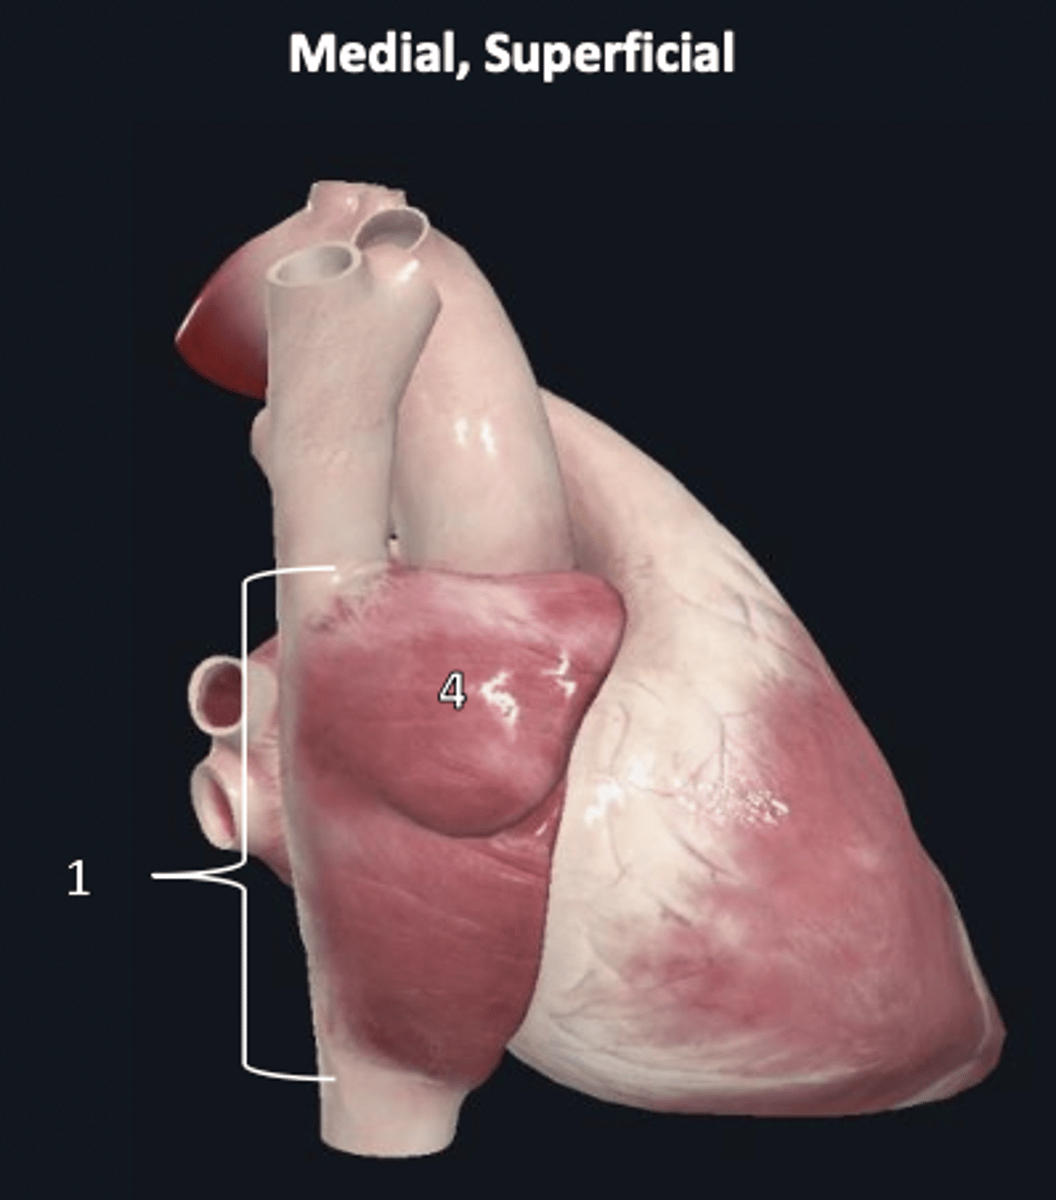

fibrous pericardium

1 (superficial)

apex

1

base

2

diaphragmatic surface

3

sternocostal surface

4

atrioventricular groove

5

anterior interventricular sulcus

6

posterior interventricular sulcus

7